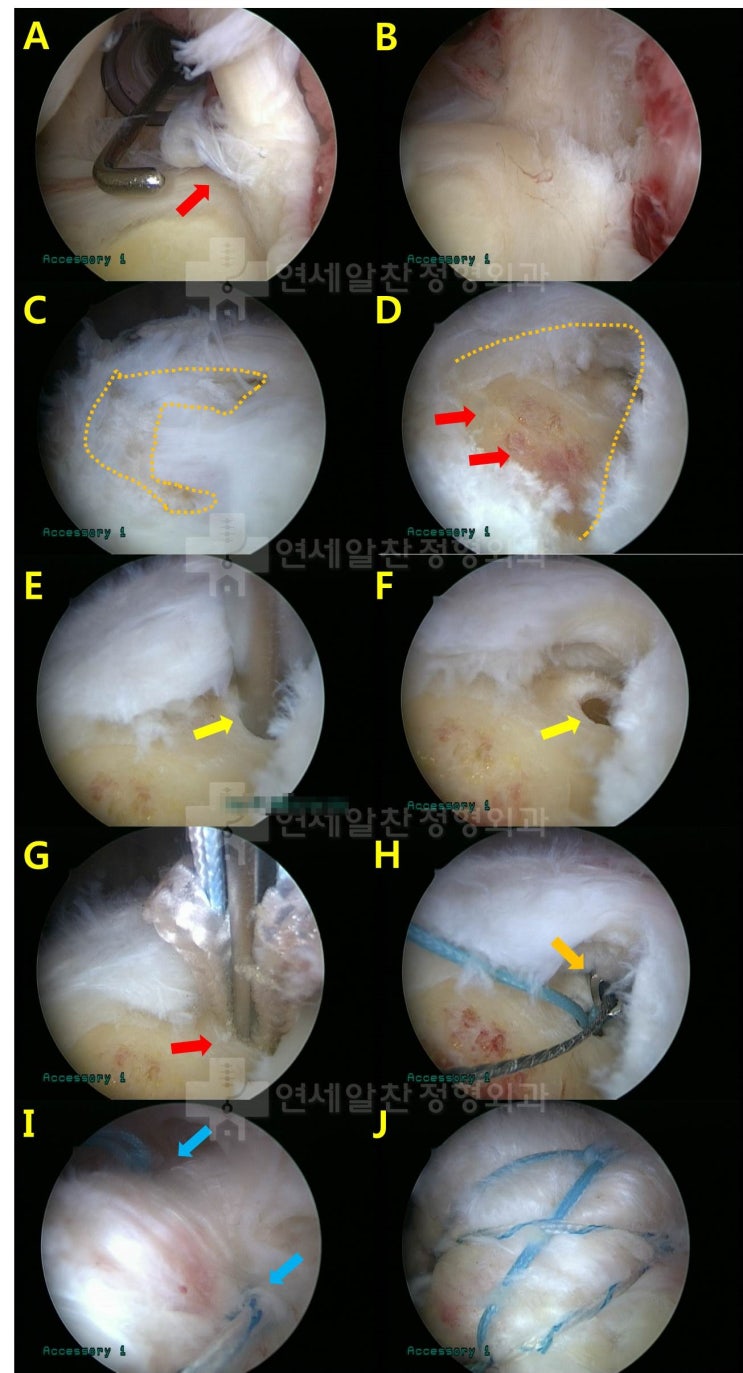

극상근 전층파열에 가까운 관절내측 파열에서 이열교량형 봉합법을 이용한 복원 및 원인에 대한 고찰

55세 여자 환자로 수개월간의 어깨 통증 및 움직임시 심한 통증을 주소로 본원으로 내원하였다. 환자는 수...